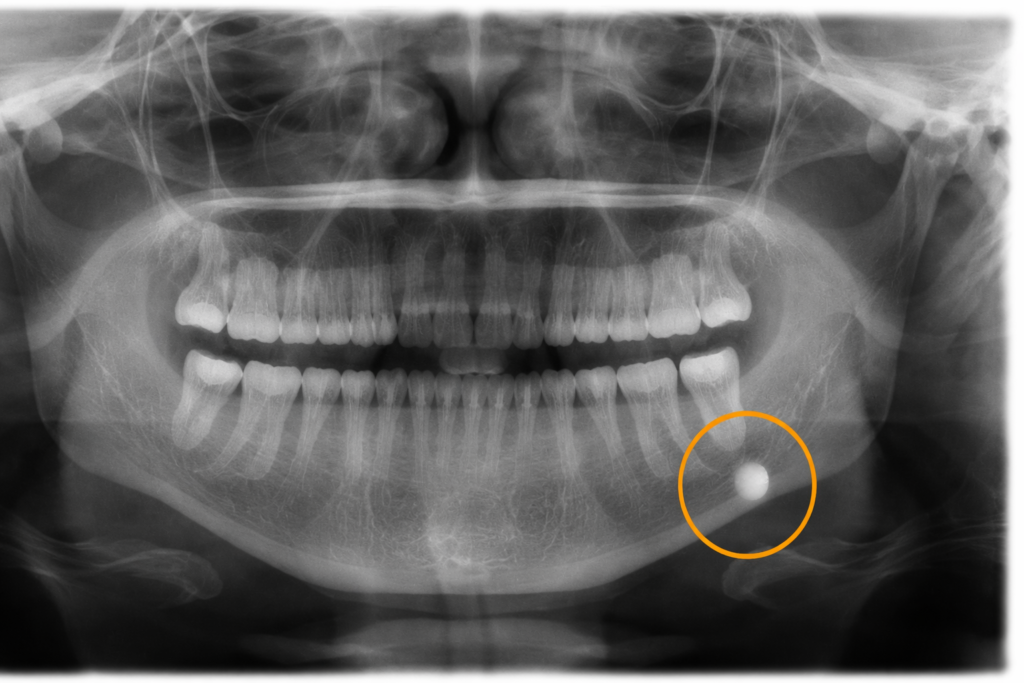

A radiografia panorâmica é amplamente utilizada na investigação de cálculos em glândulas salivares, principalmente na glândula submandibular.

Os sialólitos costumam se apresentar como imagens radiopacas bem delimitadas, localizadas próximas ao assoalho bucal ou à região do ângulo mandibular.

Apesar de sua utilidade, a radiografia panorâmica pode não identificar cálculos pouco mineralizados ou de pequenas dimensões.

O diagnóstico diferencial dos cálculos s inclui linfonodos calcificados, flebólitos, calcificações distróficas e lesões odontogênicas projetadas sobre áreas anatômicas semelhantes.

A análise criteriosa da localização, forma e relação anatômica da imagem é indispensável.